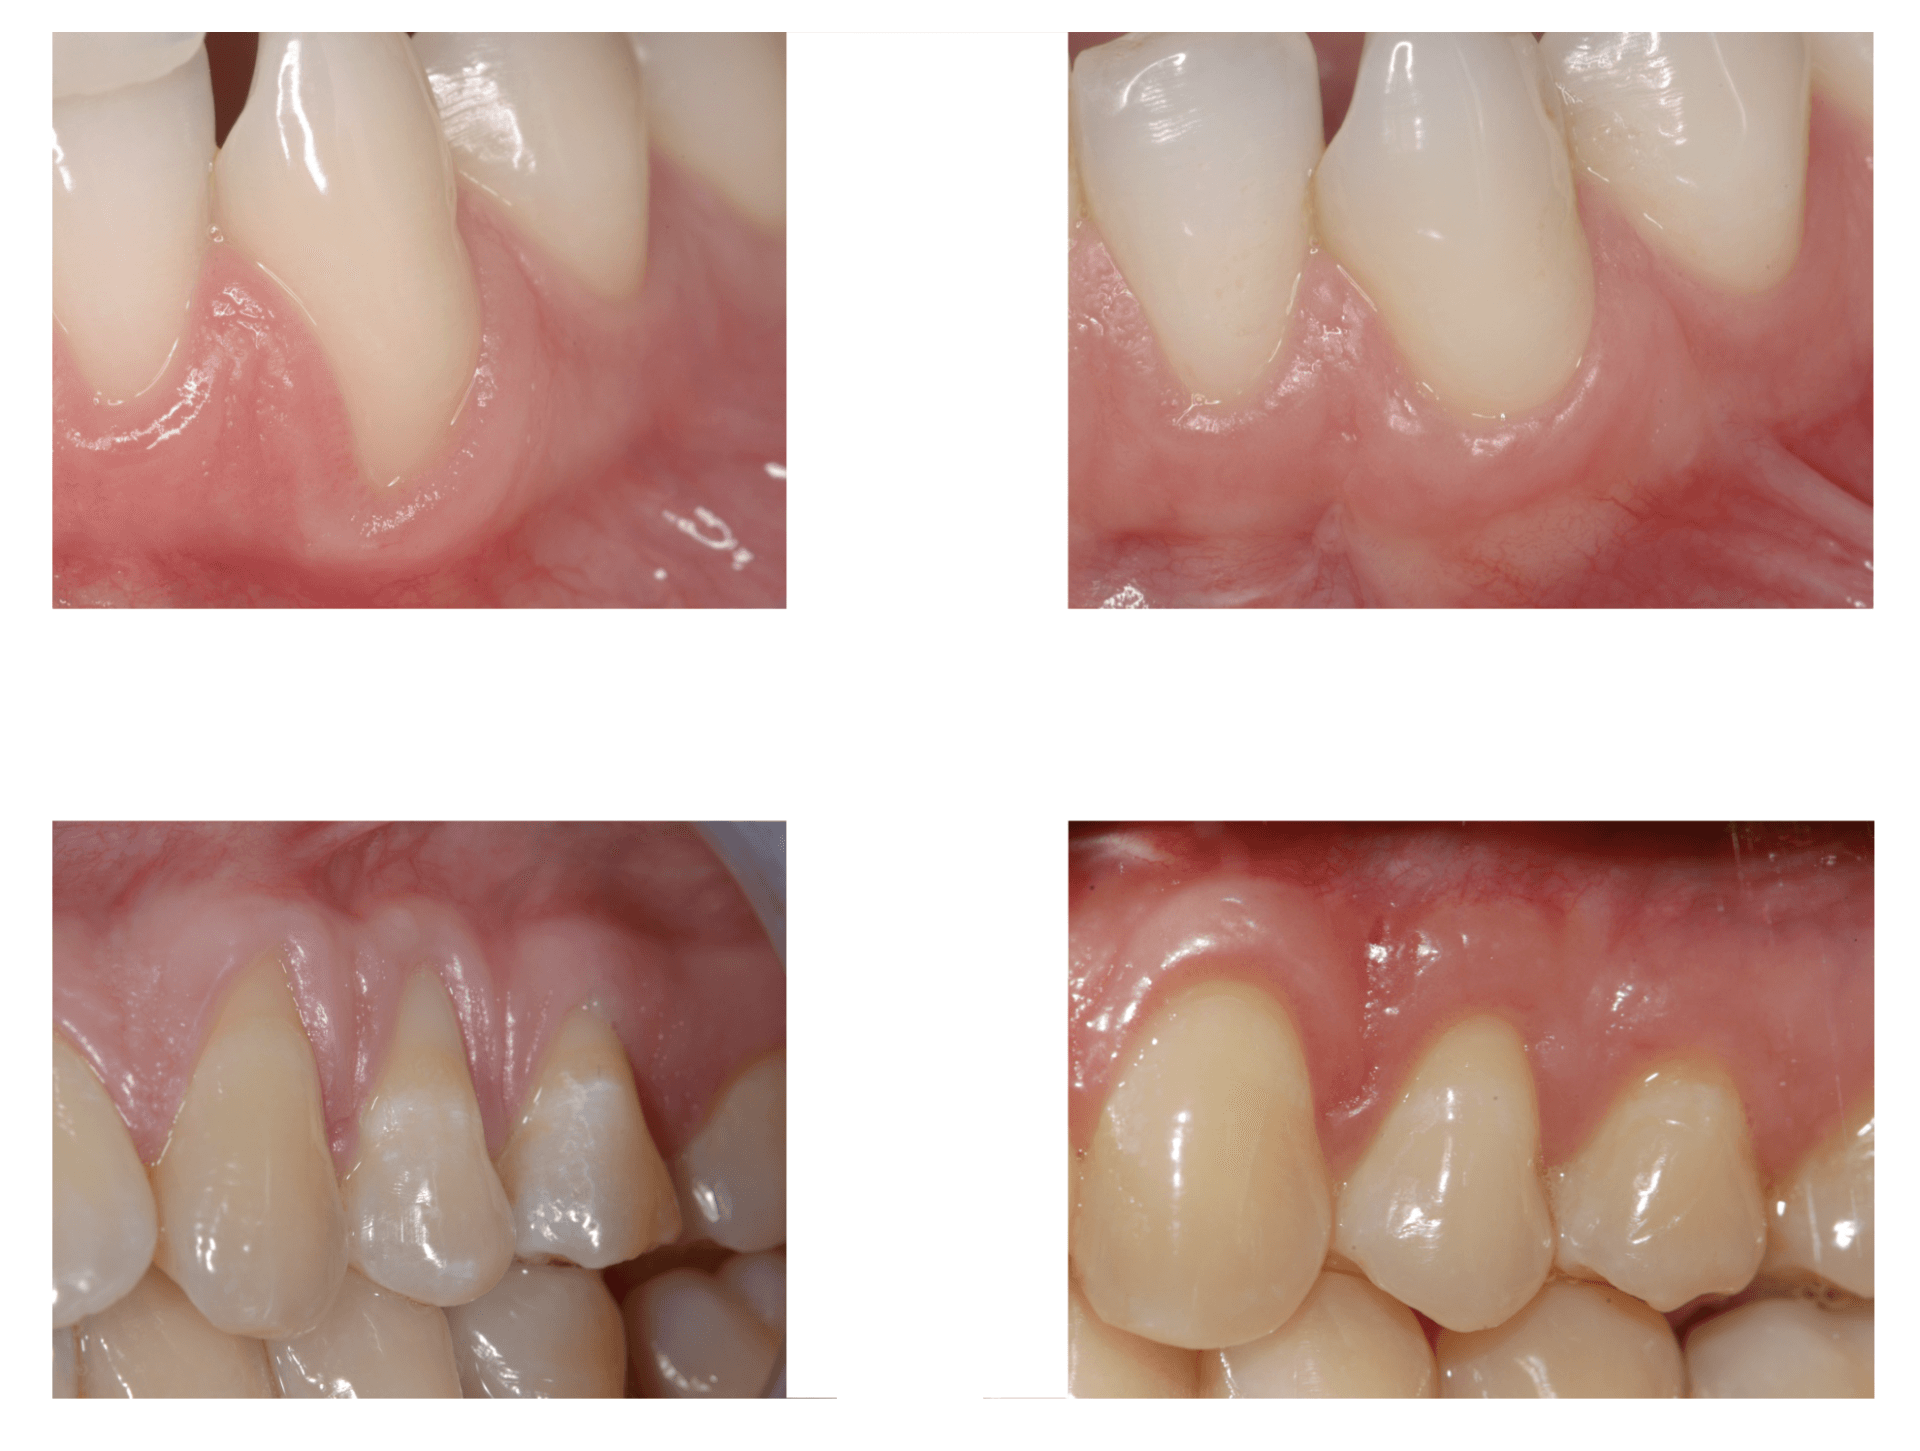

La malattia gengivale è un processo infiammatorio caratterizzato da un accentuato arrossamento, da gonfiore e sanguinamento della gengiva. La forma iniziale è la gengivite, un’infiammazione delle gengive causata da un accumulo di placca batterica. Se il paziente non osserva le manovre corrette di igiene e i controlli professionali, essa può progredire fino ad una condizione grave in cui il processo infiammatorio si estende in profondità fino all’osso di sostegno: la parodontite.

Questa patologia rappresenta una delle cause della perdita di tessuto connettivo, del riassorbimento dell’osso alveolare e della formazione di tasche parodontali che possono condurre alla perdita dei denti ed è una delle cause più comuni della perdita dei denti negli adulti. Grazie alla chirurgia orale per queste tipologie di malattie infiammatorie che colpiscono il tessuto di sostegno del dente, vengono eseguiti dei trattamenti parodontali come il curettage ( ossia il procedimento di rimozione del tartaro o della placca dalla parete orale al di sotto della gengiva) o la levigatura delle radici a cielo aperto, o ancora interventi definiti rigenerativi per l’aumento dello spessore osseo, innesti gengivali, rimozioni di cisti dentali o tumori del cavo orale. Questa tipologia d’intervento consente di ricostruire il tessuto danneggiato o perso e può avvenire in contemporanea all’intervento implantare (rigenerazione ossea perimplantare) o prima di effettuare l’intervento stesso ( rigenerazione ossea preimplantare). La rigenerazione ossea può avvenire in due modi: tramite l’auto trapianto osseo, ossia il prelievo dell’osso da una parte del corpo del paziente e l’innesto nella gengiva, oppure si procede con l’applicazione di osso artificiale, realizzato in materiale sintetico e biocompatibile, che istallato nella gengiva e ricoperto da una membrana riassorbibile, si integra perfettamente con l’osso. Il nostro studio medico dentistico, grazie alla consolidata collaborazione con il dipartimento di parodontologia della facoltà di Odontoiatria dell’Università “La Sapienza “ di Roma e alla comprovata esperienza nel campo implantologico e parodontale è in grado d’intervenire con entrambe le modalità, garantendo al paziente la massima efficienza